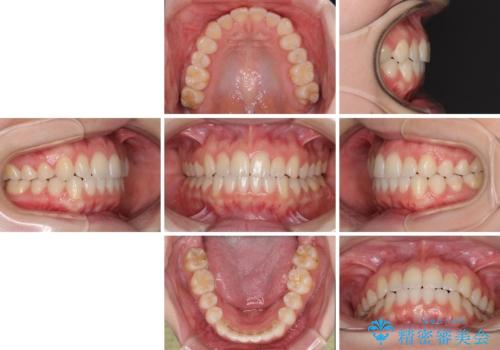

上の前歯が下の前歯を乗り越える際、奥歯がほとんど咬めない時期があり、乗り越えた後も、インビザライン特有の奥歯の咬みにくさが続きました。

咬み合わせ改善のために治療期間を要しましたが、最終的に奥歯はしっかりと咬めるようになりました。